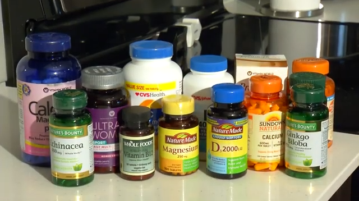

ORLANDO, Fla. (Ivanhoe Newswire) — About 59 million Americans use some type of vitamins or…More